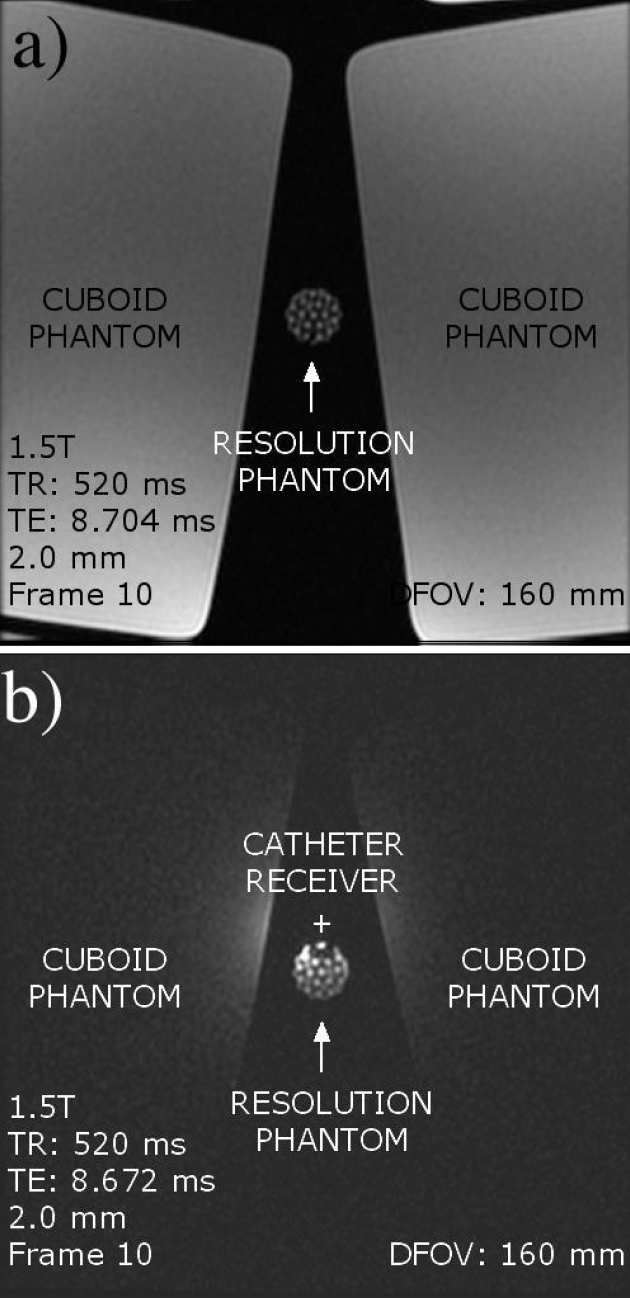

Richard Syms, Ian Young, Marc Rea

We have developed frequency-scaling rules for catheter-based magneto-inductive magnetic resonance imaging detectors, intended for in vivo imaging of the vascular and biliary ductal systems. The design is based on a cascade of magnetically coupled L-C resonators, fabricated as a thin-film circuit and mounted on a catheter. Intrinsic safety is introduced using resonant elements designed to avoid coupling to uniform RF magnetic and electric fields. We have used these rules to demonstrate frequency scaling of developed designs from 1.5 T to 3 T, and carried out mapping of reception patterns and high-resolution 1H imaging in a 3 T clinical scanner.

|---|

| CAD layout, PCB, completed catheter and inductive coupling transducer for a magneto-inductive catheter receiver. |

|---|

| Frequency response of catheter receivers designed for operation at 1.5T and 3 T. |

|---|

| Coronal image of cuboid phantom obtained with an MI catheter receiver, and reception pattern reconstructed from coronal images. |